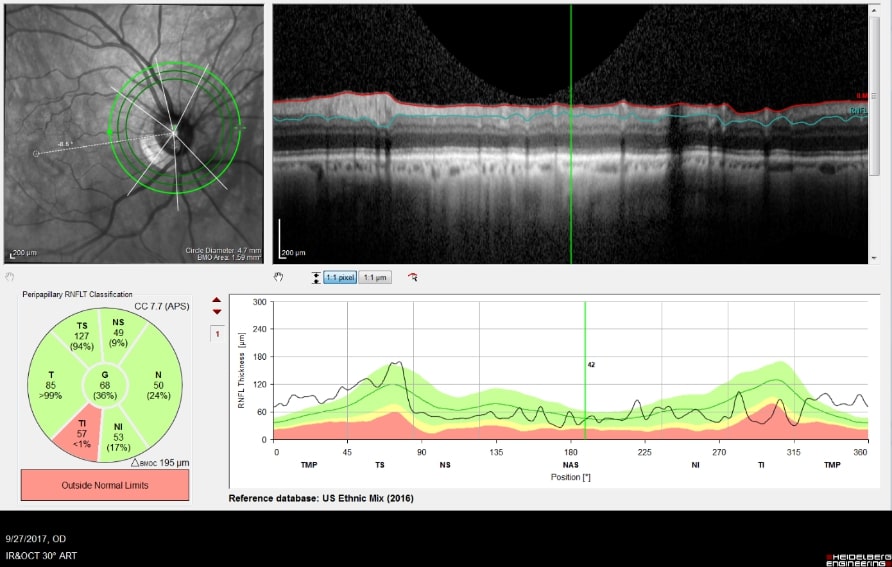

Optical Coherence Tomography (OCT) is an advanced imaging technology that has revolutionized the diagnosis and management of eye disease, especially glaucoma and retinal disease. OCT is a non-invasive method of imaging structures in the eye at an extremely high, microscopic resolution.

OCT uses infrared light to create cross-sectional, three-dimensional images of the tissues in the eye. As is the case for laser treatments, the eye is particularly amenable to imaging with OCT because the eye is optically transparent.

OCT Imaging of the Nerve Fiber Layer

OCT Image of the Retina

OCT is used in glaucoma to image the optic nerve and the nerve fiber layer in order to determine if there is damage from increased eye pressure. Because the resolution of OCT is so high, it can detect fine changes to the shape of optic nerve. Thinning of the nerve fiber layer is a sign that glaucoma is worsening and that the eye pressure is too high.

Structural changes to the optic nerve or nerve fiber layer usually precede visual field loss. In many cases, 50% of the optic nerve can be damaged before visual field loss develops. As a result, OCT is a critical tool for diagnosing glaucoma at its earliest stages.

An example of an optic nerve with glaucoma damage imaged with both fundus photography and OCT and compared to the visual field in order to demonstrate the strucure-function relationship.

The lower half of the optc nerve has early damage, and this correlates with the small superior scotoma seen on the visual field test.